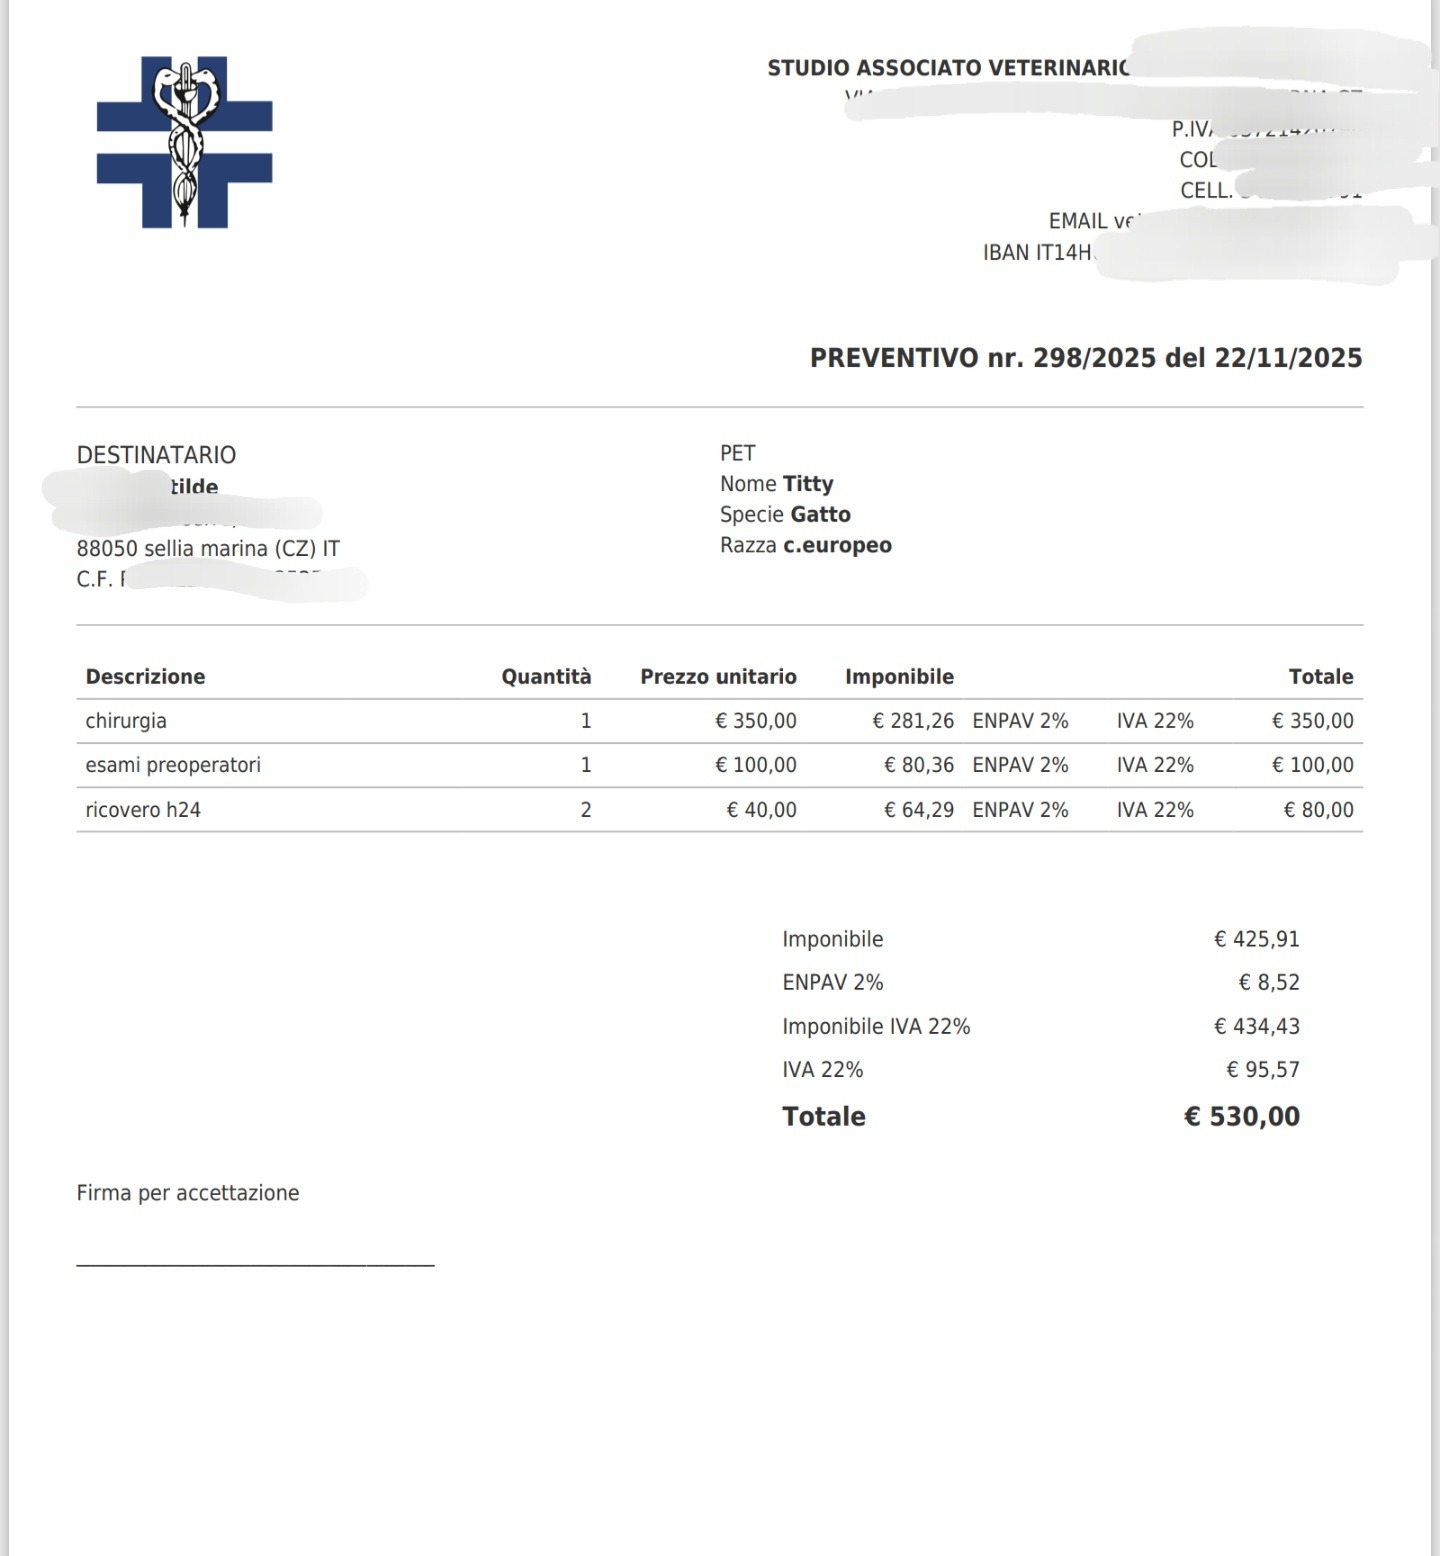

Sono stati fatti un sacco di esami ed eco, tra cui è risultata Positiva alla fiv, è stata prontamente sterilizzata dalla sua tata Ilde, ma purtroppo le disgrazie non finiscono qui, Titty ha un'ernia che va operata con urgenza, il costo dell'intervento più esami e degenza è quello che vedete nel preventivo, abbiamo bisogno di una mano per le spese